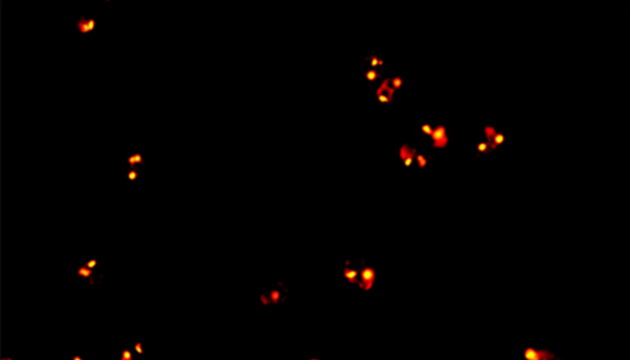

CTC檢測用于上皮腫瘤,如胃腸癌、皮膚癌等。檢測分四步:富集、CD45染白細(xì)胞、CK染CTC、DAPI染核。有DAPI、CK熒光且無CD45熒光,大核細(xì)胞為CTC;有DAPI、CD45熒光為白細(xì)胞。

MF43-N用于CTC檢測